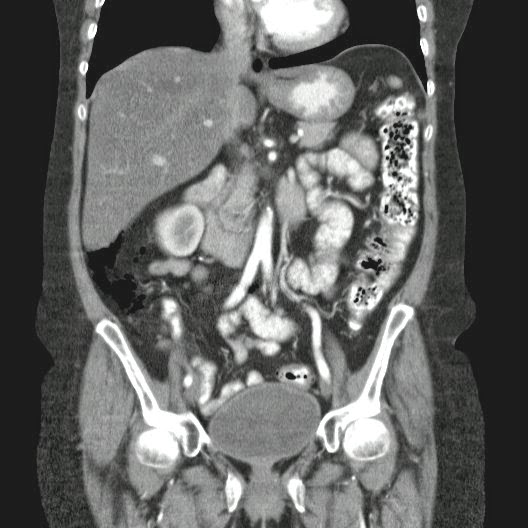

Caso Interesante #1

INGRESO

Paciente con antecedente de ALIF (Fusión lumbar intersomática anterior) 360 grados L5-S1 hace siete meses, quién presenta herida de abordaje anterior con dehiscencia de sutura, con cierre por segunda intención, quien consulta por cuadro clínico de dos días de secreción purulenta en herida quirúrgica, niega fiebre, niega otras sintomatología, refiere episodios previos similares.

EVOLUCIÓN

Paciente en POP de ALIF L5-S1 quien presento dehiscencia de la herida abdominal con ISO superficial ya tratada, sin embargo persiste con dehiscencia y desde ayer con supuración asociado a fiebre subjetiva. Se realiza eco abdominal con colección en pared sugestiva de absceso, elevación de RFA por lo cual se considera se debe hospitalizar para manejo antibiótico, drenaje de la colección, manejo médico y vigilancia neurológica.

- ¿Hallazgos Escanografia?